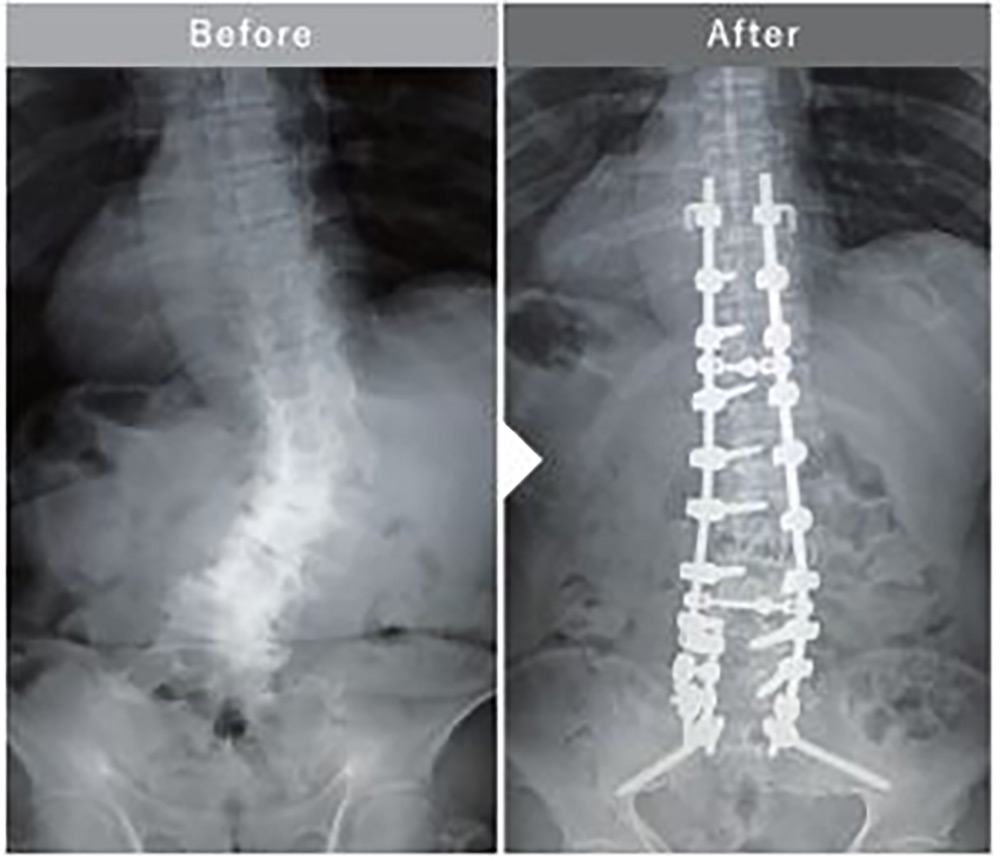

成人脊柱変形に対する胸腰仙椎矯正固定術